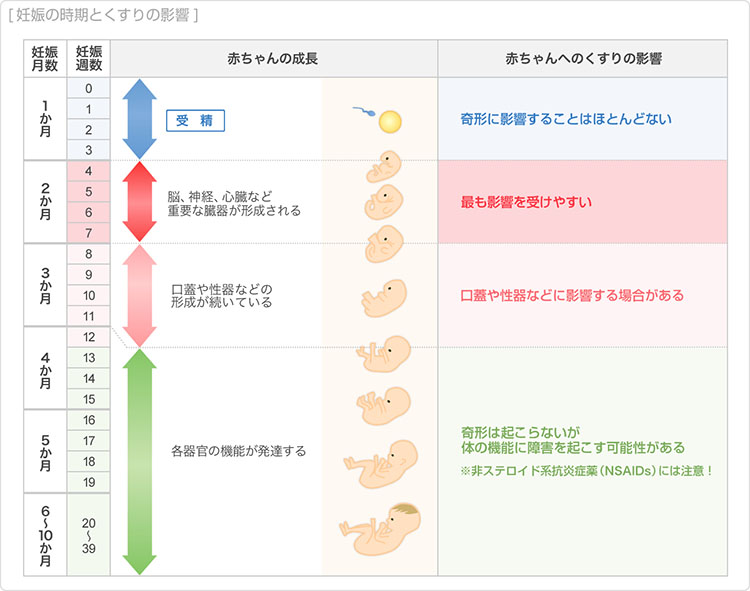

胎児の発育状況 (319 無料写真)

母子手帳「胎児発育曲線 新生児の成長曲線 」の見方と活用法-おむつのムーニー 公式 ユニ・チャーム。

医師監修 胎児の発育曲線 成長曲線 とは?どのように見ればいいの?ゼクシィBaby。

胎児発育曲線』とは?週ごとの発育の目安を助産師が解説◎ - 株式会社エバーセンス。

胎児発育曲線』とは?週ごとの発育の目安を助産師が解説◎ - 株式会社エバーセンス。

胎児発育曲線の±2.0SDの意味は?エコー写真に学ぶ統計学 - 日常を少し掘り下げてみる。

医師監修 おなかの赤ちゃんの発育は順調? 「胎児発育曲線」とはトモニテ。

胎児発育曲線の±2.0SDの意味は?エコー写真に学ぶ統計学 - 日常を少し掘り下げてみる。

母子手帳「胎児発育曲線 新生児の成長曲線 」の見方と活用法-おむつのムーニー 公式 ユニ・チャーム。